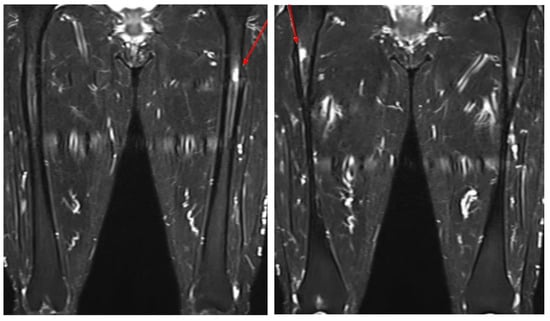

| 1 | Our case | F, 64 | O/O | Simultaneous | Ibandronate 150 mg monthly for 10 years | Prox/prox | PIM nailing/PIM nailing | Teriparatide | NA |

| 23 | Kosuke Hamahashi et al., 2020 [29] | F, 57 | O/O | Simultaneous | Zoledronic acid for 10 years | Prox/prox | IM nailing/PIM nailing | NA | 24 months/ 15 months |

| 24 | F, 57 | X/X | Sequential (3 years) | Alendronate for more than 10 years | Prox/prox | IM nailing/IM nailing | NA | 25 months/ 58 months | |